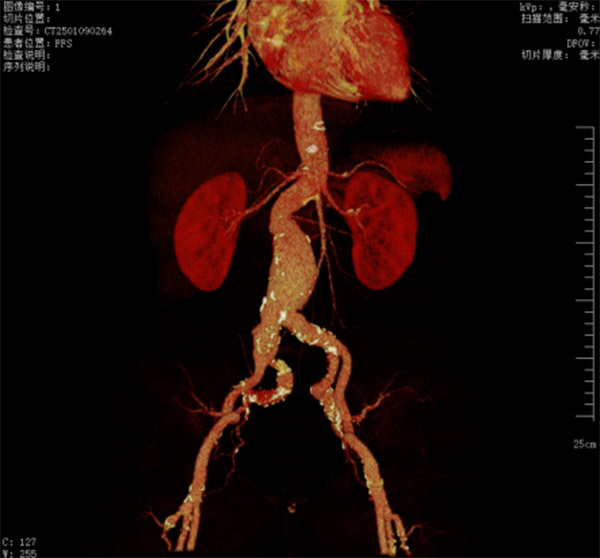

67岁的李先生,因腰部疼痛,来我院就诊。入院后经检查确诊腹主动脉瘤。腹主动脉瘤的诊断一旦确立,就要及时治疗,防止这颗“不定时炸弹”随时引爆。经过腹主动脉的CTA检查发现,李先生腹主动脉瘤伴腹壁血栓及双侧髂总动脉瘤并伴有多发大动脉粥样硬化改变。大多数动脉瘤患者并无特别的临床症状,但动脉瘤一旦破裂,患者常常会因为大出血而猝死。因此家属决定实施手术治疗。在完善各项术前检查、评估后,肿瘤介入科张申众主任带领团队经过反复讨论和精心规划,为患者制定了详尽周全的手术方案。

术前CTA